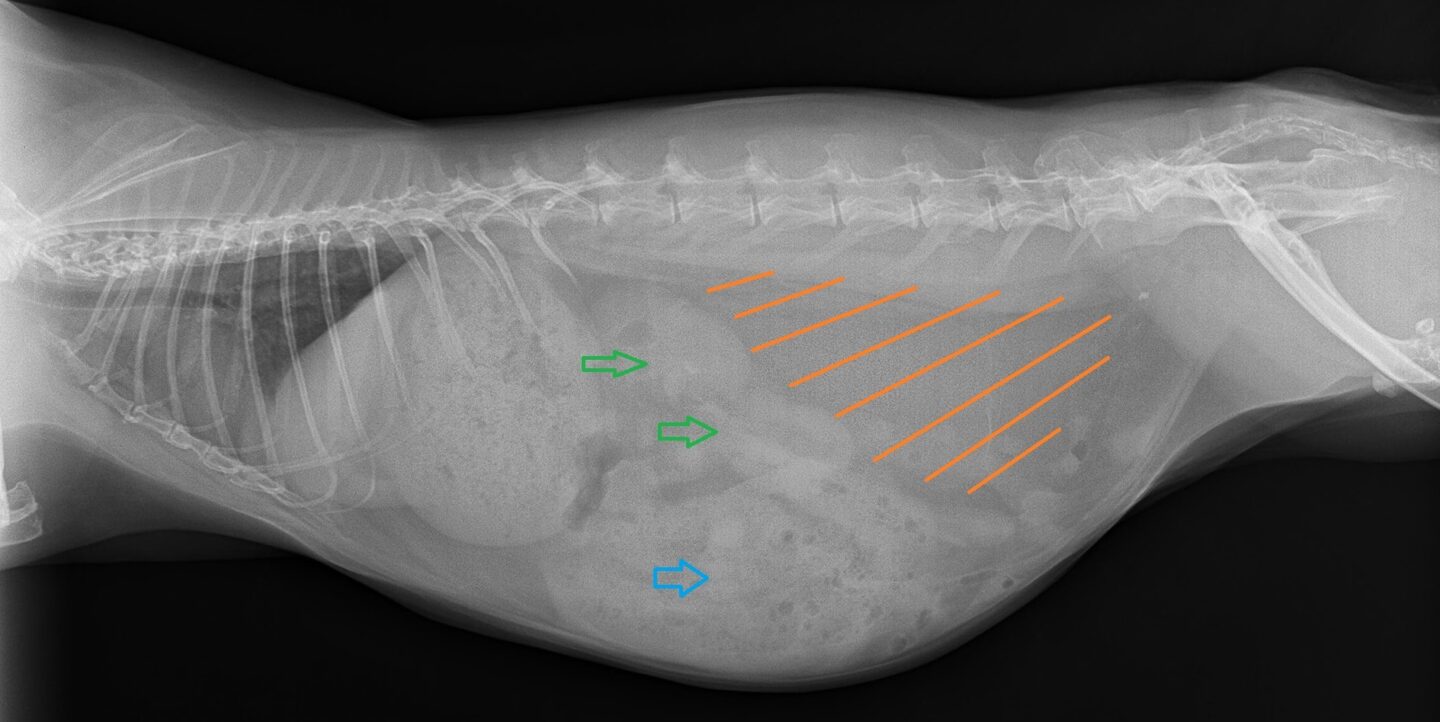

Kaninchen und Meerschweinchen als Notfall - Besonderheiten beim Röntgen

Immer mehr Halter:innen von Kaninchen und Meerschweinchen erwarten für ihre Tiere eine genauso gute tiermedizinische Versorgung, wie sie es für Hunde oder Katzen mittlerweile Standard in unseren Praxen ist. Auch die Bereitschaft, diese Leistungen zu bezahlen, ist da. Viele Halter:innen fahren sogar hunderte Kilometer, um ihre Tiere bei einem entsprechend fortgebildeten Tierärzt:innen vorzustellen. Im Notdienst oder bei akuten lebensbedrohlichen Erkrankungen ist das nicht möglich, und Kaninchen und Meerschweinchen werden Kolleg:innen notfallmäßig vorgestellt, die nicht umfassend in di